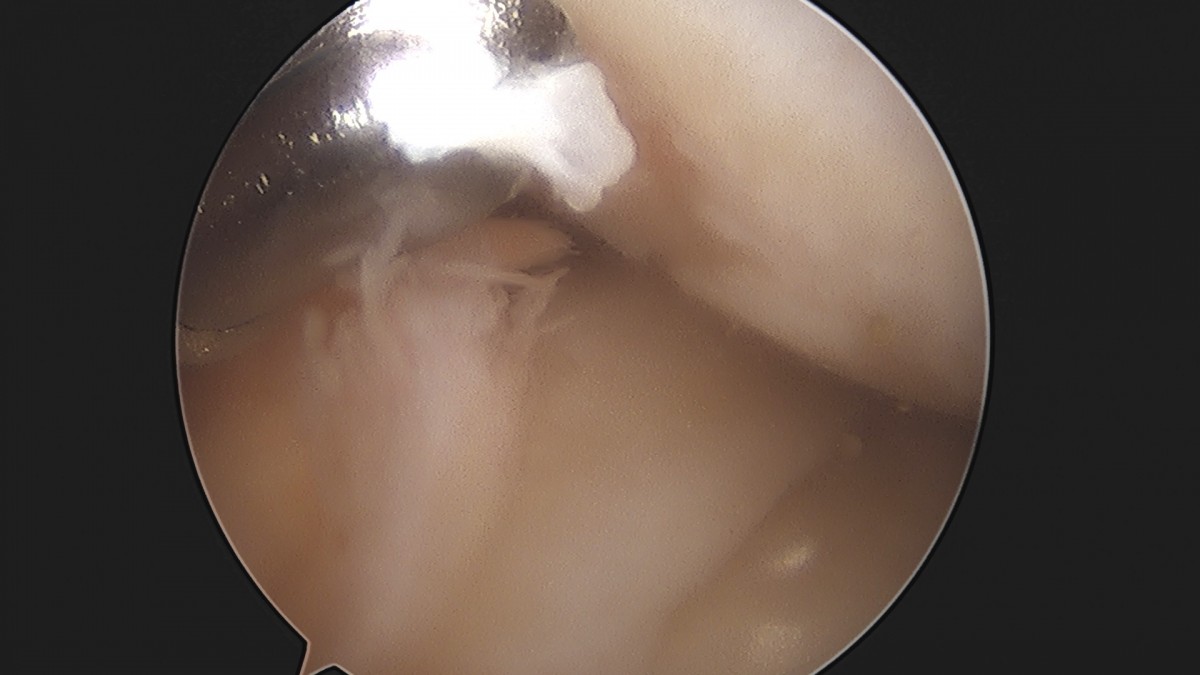

이재상원장님 무릎 반월상 연골판 절제술 김민O 환자

작성자 최고관리자 댓글 0건 조회 365회 작성일 25-09-16 16:10